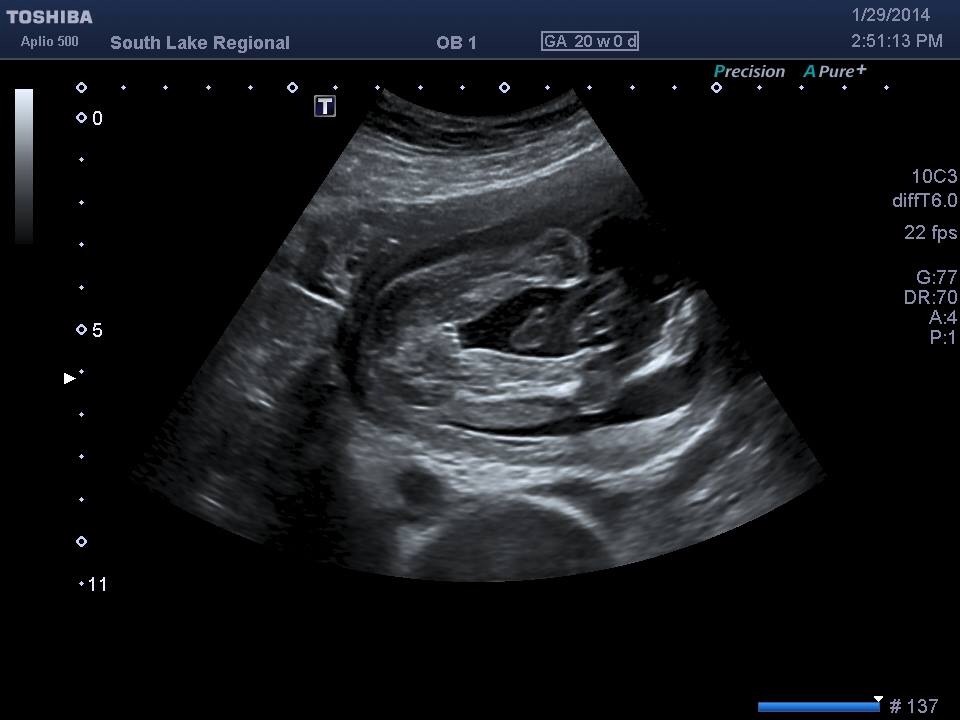

I thought to share my confirmed pics...from early on most guessed girl from skull and nub theory...hope everyone is doing fantastic :)Attachment 16855Attachment 16856Attachment 16857